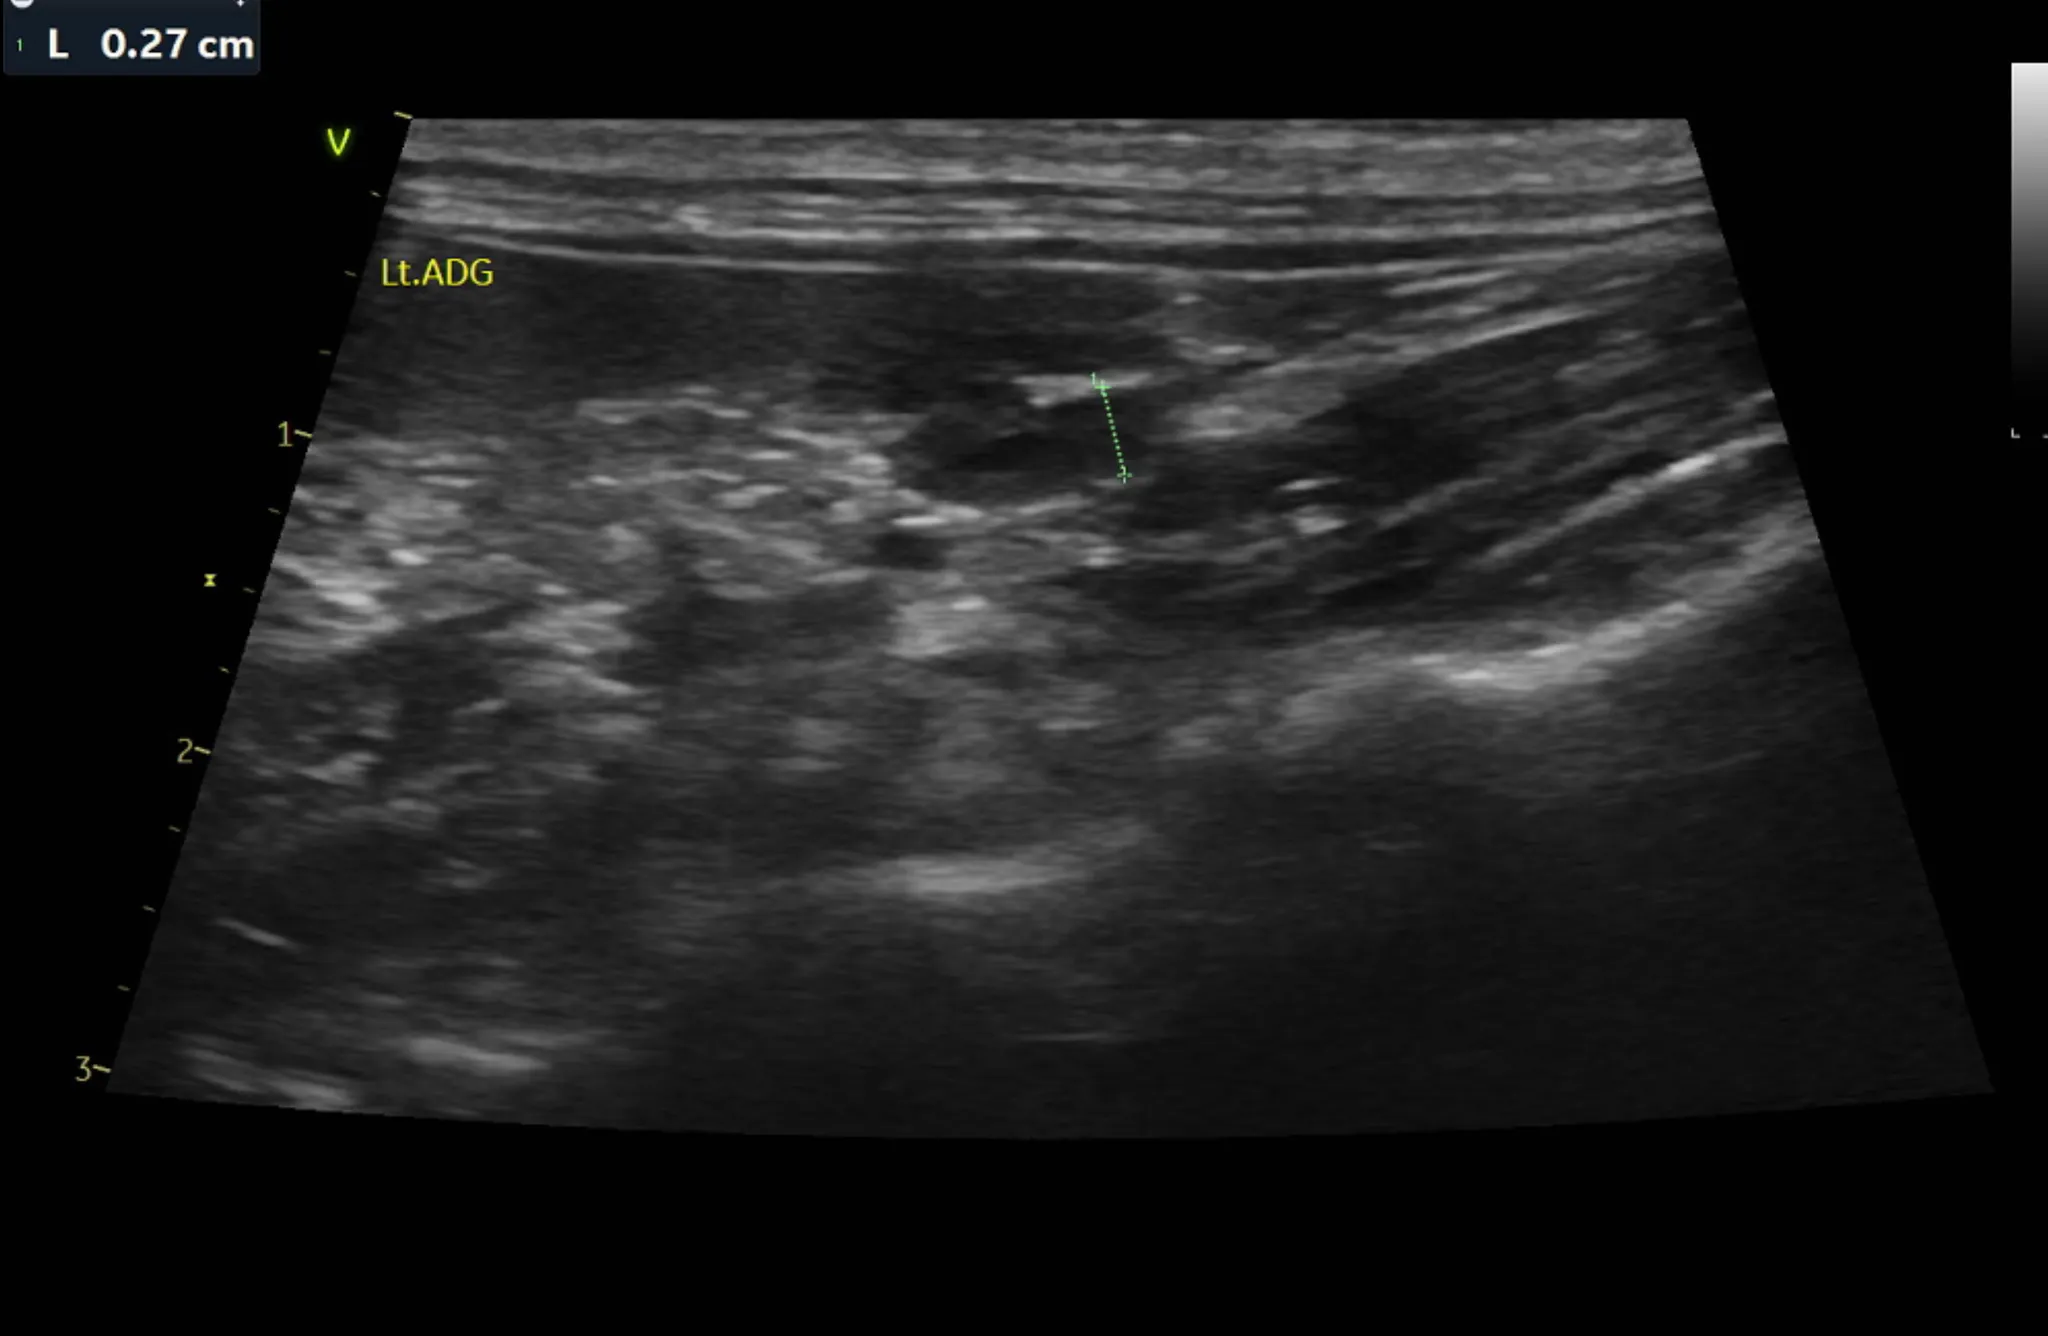

3. 복부 초음파 검사 결과

복부 초음파 검사로는 간, 신장 등 복부 장기의 모양과 결석, 종양등의 이상여부를 알 수 있습니다.

또한 방광 결석, 다낭포성 신장질환 같은 고양이에서 잘 생기는 질환의 경우 초음파 검사로만 알 수 있으므로 매우 중요한 검사 중 하나입니다.

•

복부 초음파 검사 상 특이사항은 발견되지 않았습니다.

1년 주기로 검사를 추천드립니다.